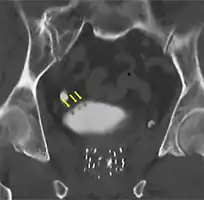

If invasive or high grade (includes carcinoma in situ) cancer is detected on TURBT, an MRI and/or CT scan of the abdomen and pelvis or urogram and CT chest or x-ray chest should be conducted for disease staging and to look for cancer spread (metastasis). Increase in alkaline phosphatase levels without evidence of liver disease should be evaluated for bone metastasis by a bone scan.[1] Although 18F-fluorodeoxyglucose (FDG)-positron emission tomography (PET)/CT has been explored as a viable method for staging, there is no consensus to support its role in routine clinical evaluations.[54]

CT Urography shows multiple tumors -